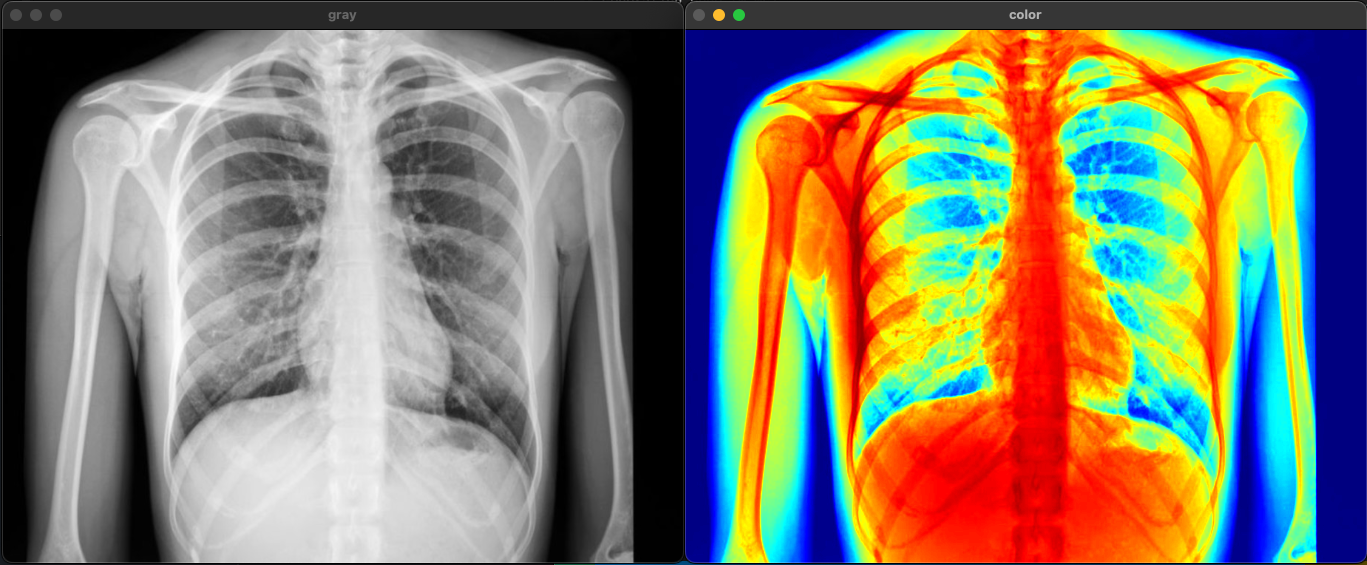

Pseudo Coloring

인간의 눈은 회색 음영은 30-50 단계만 구분할 수 있지만 색은 100k ~ 10m 가지까지 구분가능하다

회색 영상에 색을 입히면 훨씬 많은 정보를 확인할 수 있다.

Color Scale을 함께 포함하여 색이 어떤 의미인지 이해할 수 있도록 해야 함

void testPseudoColoring() {

Mat gray = imread("xray.png", 0);

Mat color;

applyColorMap(gray, color, COLORMAP_JET);

imshow("gray", gray);

imshow("color", color);

waitKey(0);

}